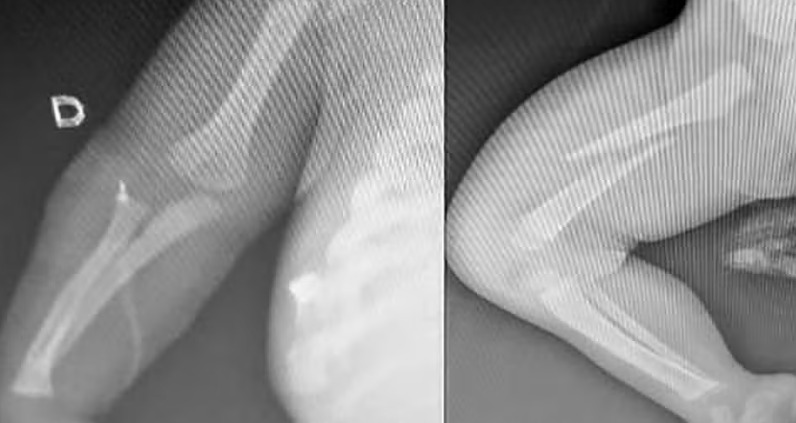

O bebê está em estado grave com fraturas nos braços, fêmur, costela, além de perfuração no pulmão e hematomas pelo corpo.

O homem chegou a dizer no hospital que a criança tinha caído da cama, enquanto dormia sobre a cabeça dele. No entanto, os exames constataram as agressões.